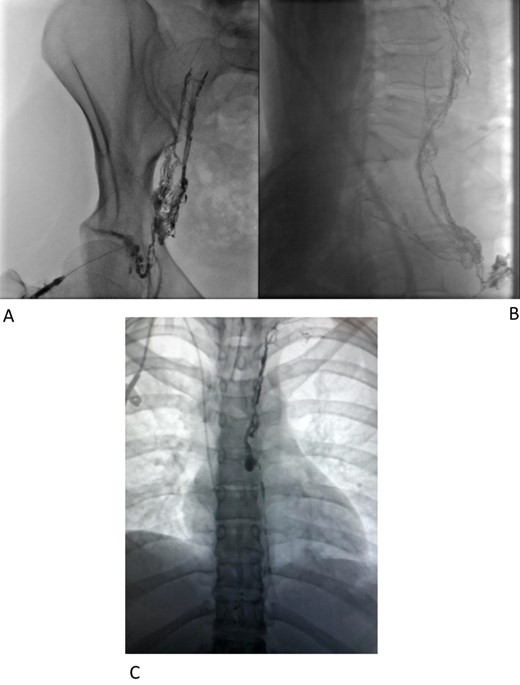

Interventional radiology was consulted for possible endovascular embolization of the thoracic duct. An intranodal lymphangiogram was performed by insertion of a needle into a right inguinal lymph node and a slow injection of Lipiodol (Fig. 1a and b). The contrast passed through the pelvis and right side of the retroperitoneum to the level of L2–L3. At this level, the contrast passed to the left side via multiple tiny collaterals. No cisterna chyli was identified, preventing this avenue to cannulation/embolization. A small calibre thoracic lymphatic duct opacified in the left paravertebral region that communicated with a focal dilatation at the level of T7. Superior to this, the lymphatics were duplicated for a short segment before reuniting (Fig. 1c) then expelling Lipiodol into the drain tube. An attempt was made to cannulate the cervical thoracic duct percutaneously under ultrasound and fluoroscopic guidance, but this could not be achieved.